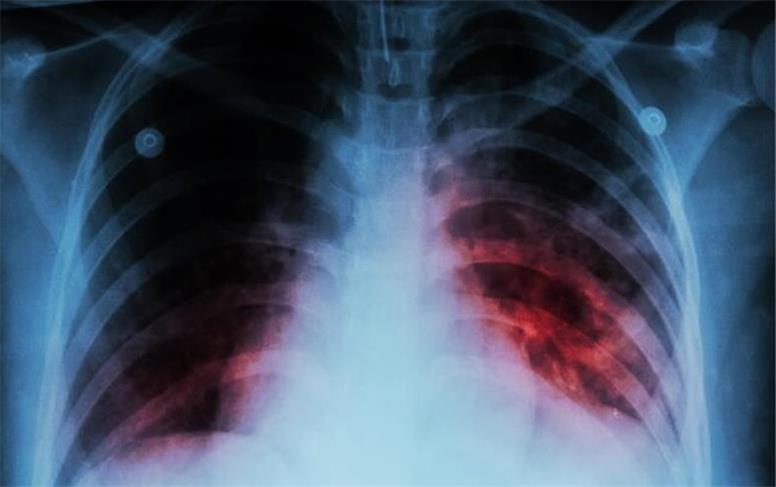

بیماری سل تا چند سال آینده ریشه کن می‌شود؟